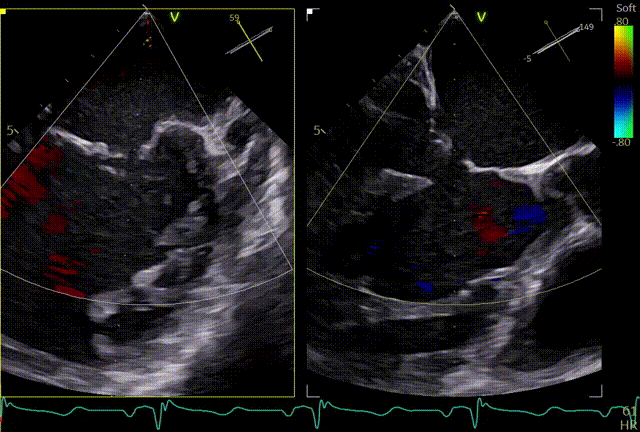

术前TEE及左房压

1区

1区带彩

2区

2区带彩

3区

3区带彩

3D

3D带彩

术前肺静脉频谱

3区gap